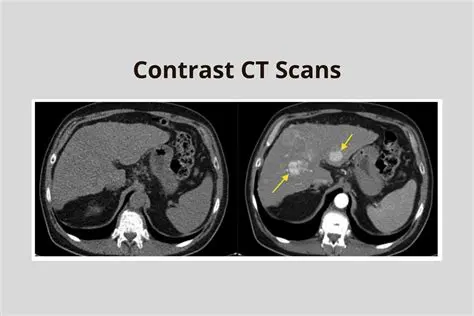

Use the correct contrast material